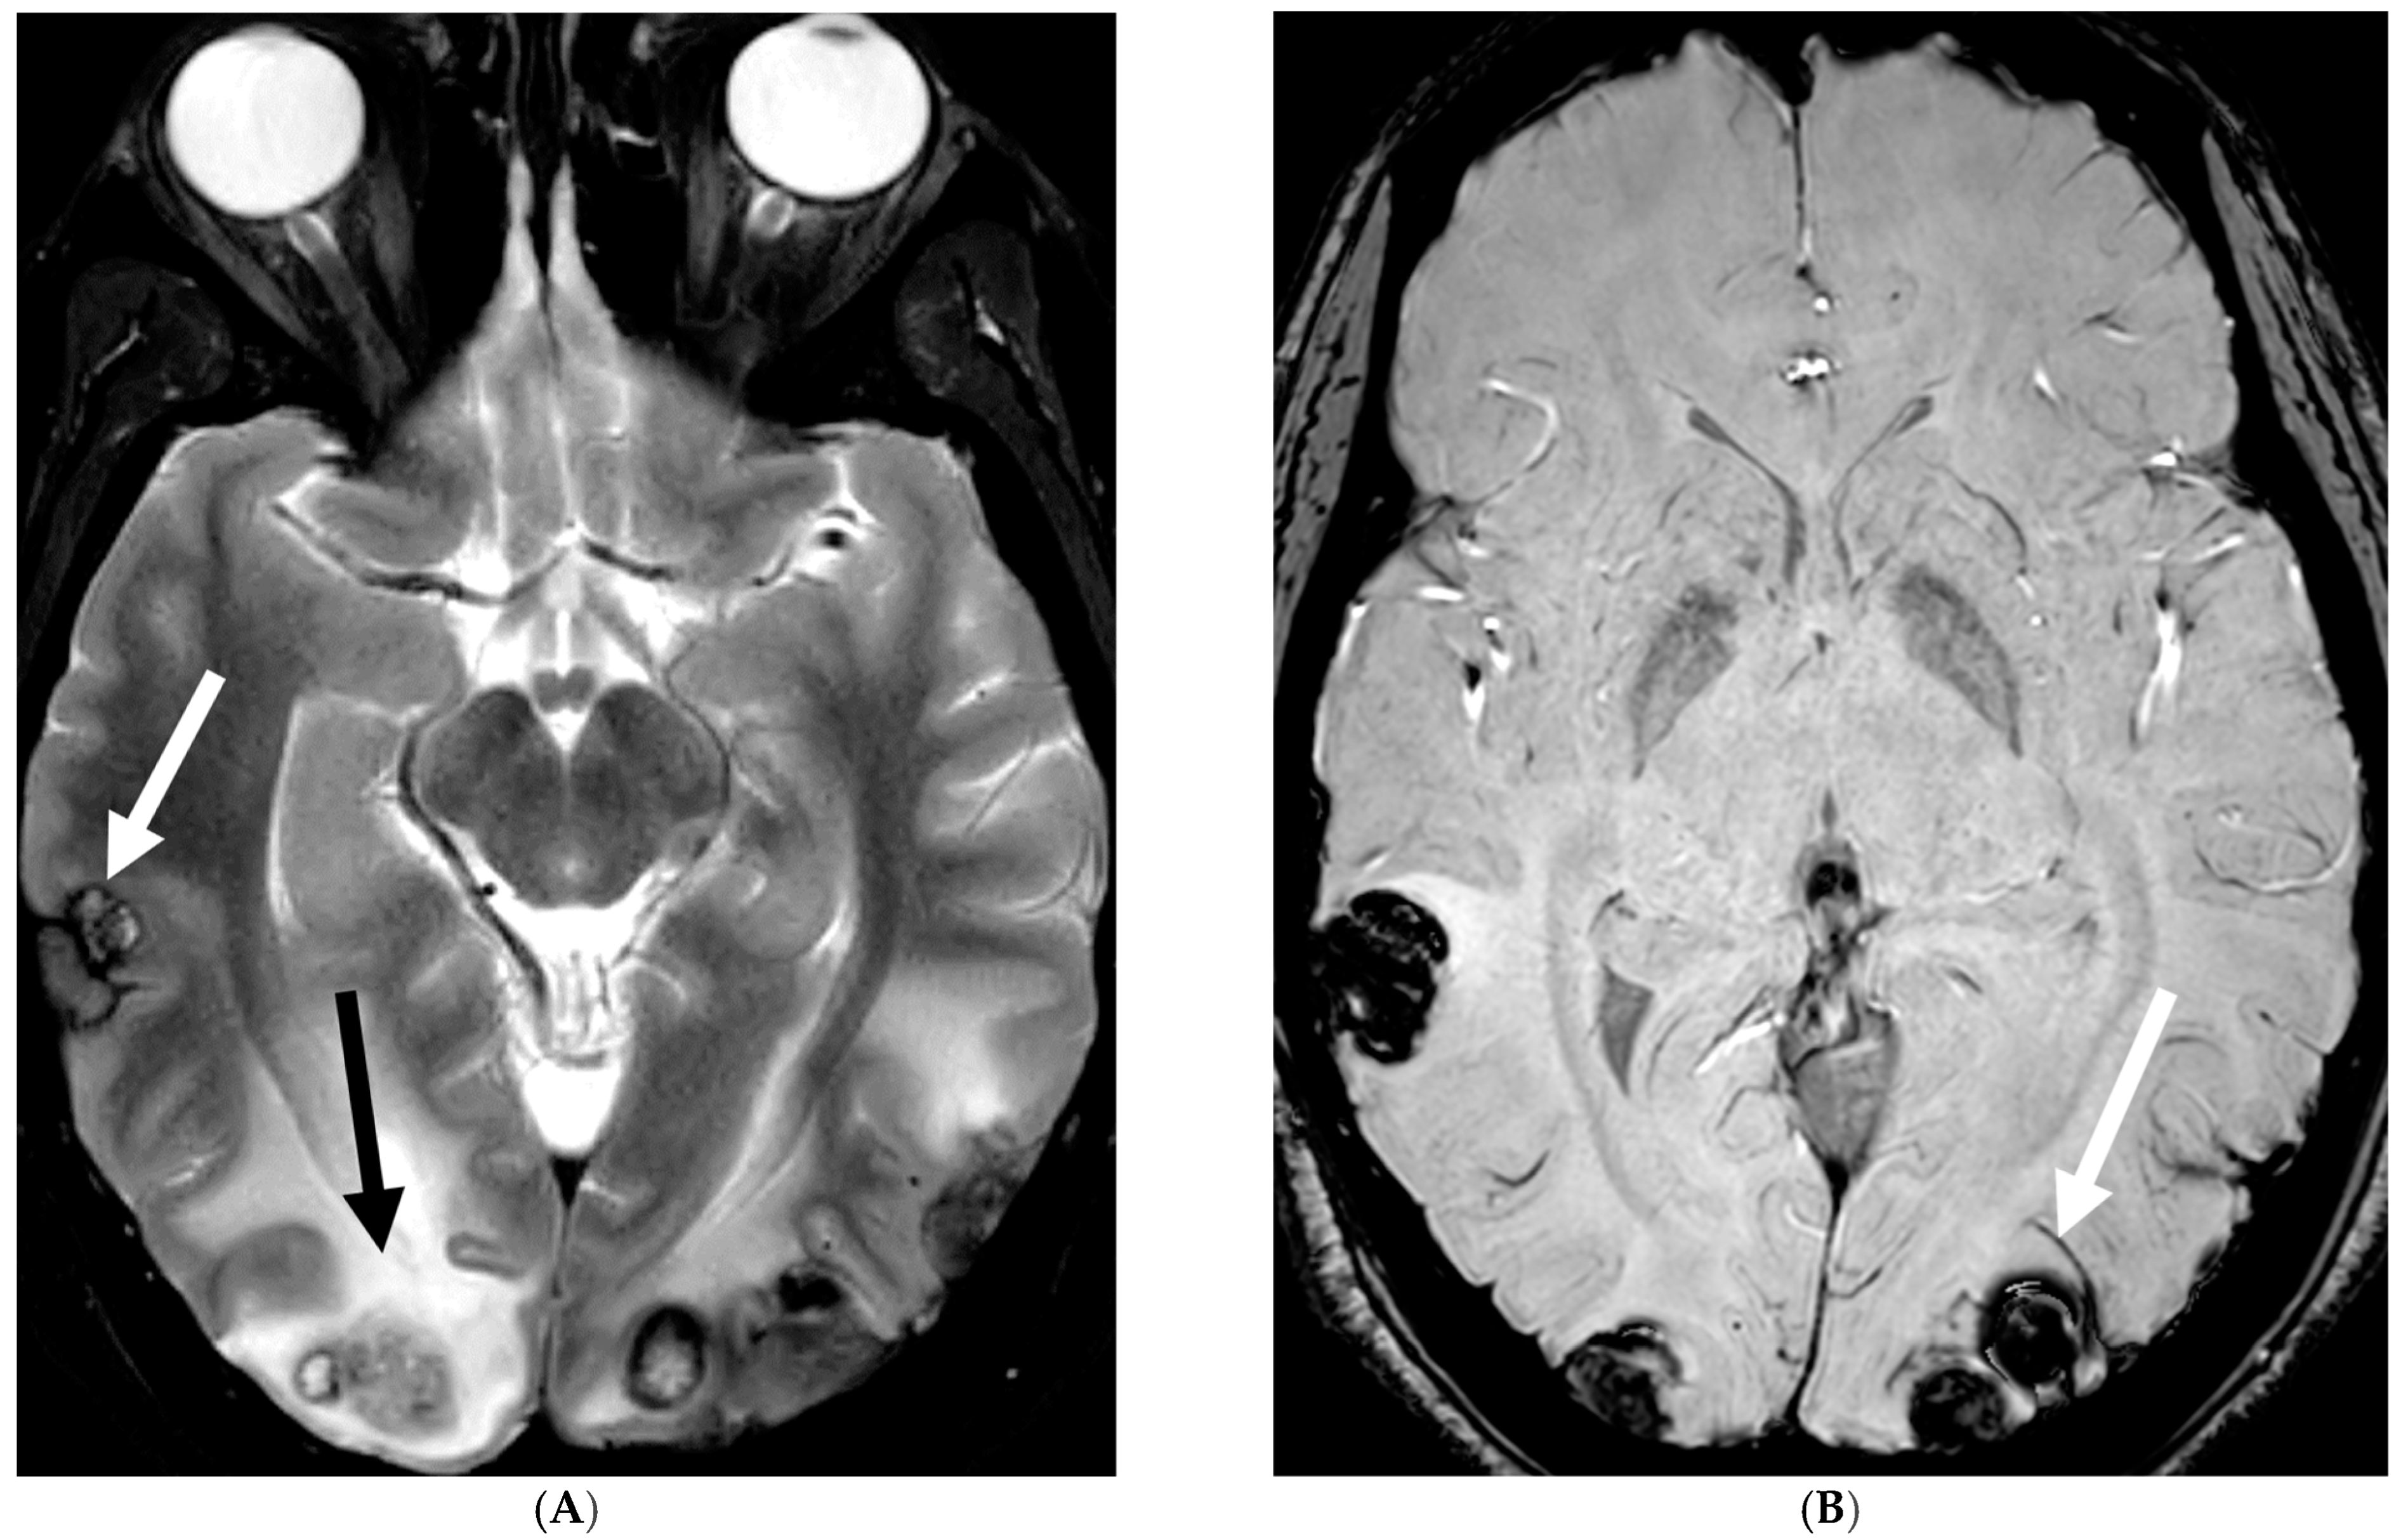

4.4. Systemic Meningeal Metastases (SMM)

Meningeal metastases from an extracranial primary tumor is a diagnosis with a grave prognosis, reducing the survival to less than 3 months if left untreated. Early and accurate diagnosis is essential for improving patient outcomes [84]. Leukemias and neuroblastoma are the most common primary malignancies in the pediatric population [85,86]. Leukemia is the only one which merits prophylactic treatment to avoid SMM.

The typical MRI presentation of SMM involves serpentine, nodular, or plaque-like enhancement in sulcal spaces, basal cisterns and along the cauda equina nerve roots [87,88]. Notably, SMM enhancement on post contrast [PC]-T1 images is superior to the PC-FLAIR in contrast to that seen in infectious meningitis [84]. However, in case of a non-enhancing primary tumor, FLAIR and DWI are important sequences to look for SMM. Hydrocephalus and subependymal deposits are other common features found in kids with SMM (Figure 15, Figure 16 and Figure 17). Positive cytology on CSF analysis, especially with leukemia, is important [89].

Figure 15.

Axial DWI (A), axial ADC (B), axial T1 FS post contrast (C) and Fluorodeoxyglucose Positron Emission Tomography (FDG–PET) scan (D): 13-year-old male with bilateral leg pains, headache, fever and weight loss: Blood tests and CT scan were concerning for Burkitt’s lymphoma. There is heterogeneous calvarial bone marrow signal with restricted diffusion (arrows) and patchy enhancement (curved arrows). Diffuse thickening and enhancement of pachymeninges in the supratentorial compartment is noted (dashed arrows). Findings are most consistent with lymphomatous involvement. Multifocal diffuse/heterogeneous pattern of FDG uptake within the axial and appendicular skeleton and the calvarium (open arrows). Intense FDG avid uptake is seen in the presacral mass (star).

Figure 16.

16-year-old female with 4 months history of globus sensation and recent botox injection of lower esophageal junction. Headache and vomiting for past week: Esophagogram (A), Axial T2 orbits (B), axial FLAIR (C) and post contrast T1 (D,E): Narrowing of the Gastroesophageal (GE) junction with beaked configuration and mild distention of the lower esophagus likely from early achalasia (black arrow). There is bilateral papilledema indicating raised ICP (dashed arrows) and sulcal hyperintensity (curved black arrows). Diffuse LME in the supra-and-infratentorial regions and along optic sheaths raising the concern for leptomeningeal carcinomatosis (white arrows). Pathology: Gastric adenocarcinoma metastasis.

Figure 17.

Axial T2 FS (A), axial Susceptibility weighted imaging (SWI) (B), axial DWI (C), post contrast sagittal and axial T1 post contrast (D,E): 19-year-old female with history of stage IV neuroblastoma, left paraspinal primary ganglioneuroblastoma, treated with chemotherapy, radiation and bone marrow transplant presents with headache. There are extensive hemorrhagic leptomeningeal masses, both supra and infratentorial region (arrows). The lesions also demonstrate restricted diffusion which could be secondary to internal hemorrhage or high cellularity of the tumor(curved arrows). The larger masses invade the cortex of both cerebral hemispheres, with surrounding vasogenic edema (black arrow). Avid enhancement of the lesions is seen along with overlying dura (dashed arrows). Features are in keeping with extensive leptomeningeal metastatic neuroblastoma.